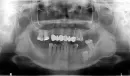

Мне советуют перед протезированием (склоняюсь к нейлоновому протезу на пару лет, т.к. зубы под мостом все испортились) провести лечение корня зуба 17.

Хотелось бы узнать Ваше мнение: действительно ли это необходимо? Врач сказал, что кариес дошел до нерва, и зуб уже все-равно мертвый — неужели это видно на снимке?

Кроме того, она хочет заменить пломбы 16, 24 и 37 (нижнего коренного). Но, если эти зубы не беспокоят, пломбы стоят на месте — действительно ли есть такая необходимость: высверливать старые и ставить новые пломбы?

Сразу отвечу на Ваш вопрос — да, на снимке четко видно, что в 17 зубе кариозная полость соединяется с полостью зуба, и если картина подтверждается визуально во рту, то однозначно можно утверждать, что нерв не совсем жив, а точнее, вероятно, мертв.

Что касается пломб, то по снимку не видно, что под ними большие полости, но однозначный ответ о необходимости замены старых пломб на новые дать не могу, потому что надо опять же изучать зондом во рту. Общая тактика такая — если пломба стоит и нет вторичного кариеса, зачем ее тогда менять? Если вторичный кариес есть, то и толка от пломбы нет, лучше поставить новую.